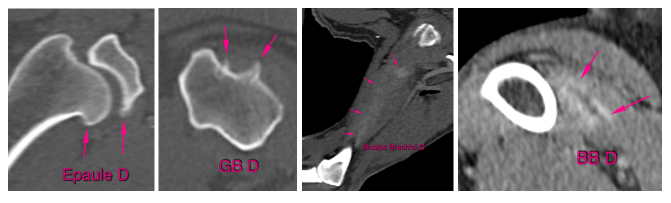

Orthopédie

Caractérisation et visualisation des fractures en 3D qui rendent la planification chirurgicale beaucoup plus précise et efficace, malformations, tendinites, ostéochondrose, fragmentation du processus coronoïde médial, hernie discale, kyste vertébral, diverticule arachnoïdien, spondylodiscite.